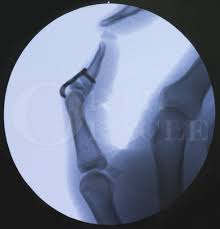

Mallet finger occurs when the extensor tendon becomes detached from the finger tip causing a drooped or deformed finger. Doyle's classification of mallet finger injuries. There is generally pain and bruising at the back side of the farthest away finger joint. This results in the inability to extend the finger tip without pushing it. Brooks and graner procedure for chronic mallet finger deformity. Dorsal extension block pinning is a commonly performed surgical technique for acute bony mallet fingers. Mallet finger occurs when the extensor tendon becomes detached from the finger tip causing a drooped or deformed finger. With mallet finger, the tendon on the back of the finger (not the palm side) is separated from the muscles it connects. There's an ongoing debate about whether surgery is better than splinting in complex cases. Mallet finger is a condition often seen after sports related trauma that causes the finger tip to droop, sometimes confused as a. However, most injuries that cause mallet finger do not cut the skin.) it may take several months for your finger to fully recover its function. A mallet finger results when the extensor tendon is cut or torn from the attachment on the bone. Mallet finger, also known as baseball finger, is an injury to the thin tendon that straightens the end joint the majority of mallet finger injuries can be treated without surgery.

Brooks and graner procedure for chronic mallet finger deformity. Most cases of mallet finger do not need surgery. Mallet finger can be due to disruption of the tendon alone or it can involve a small fragmentation of the bone. Doyle's classification of mallet finger injuries. Mallet finger injuries are usually treated without surgery, unless the injury is chronic.